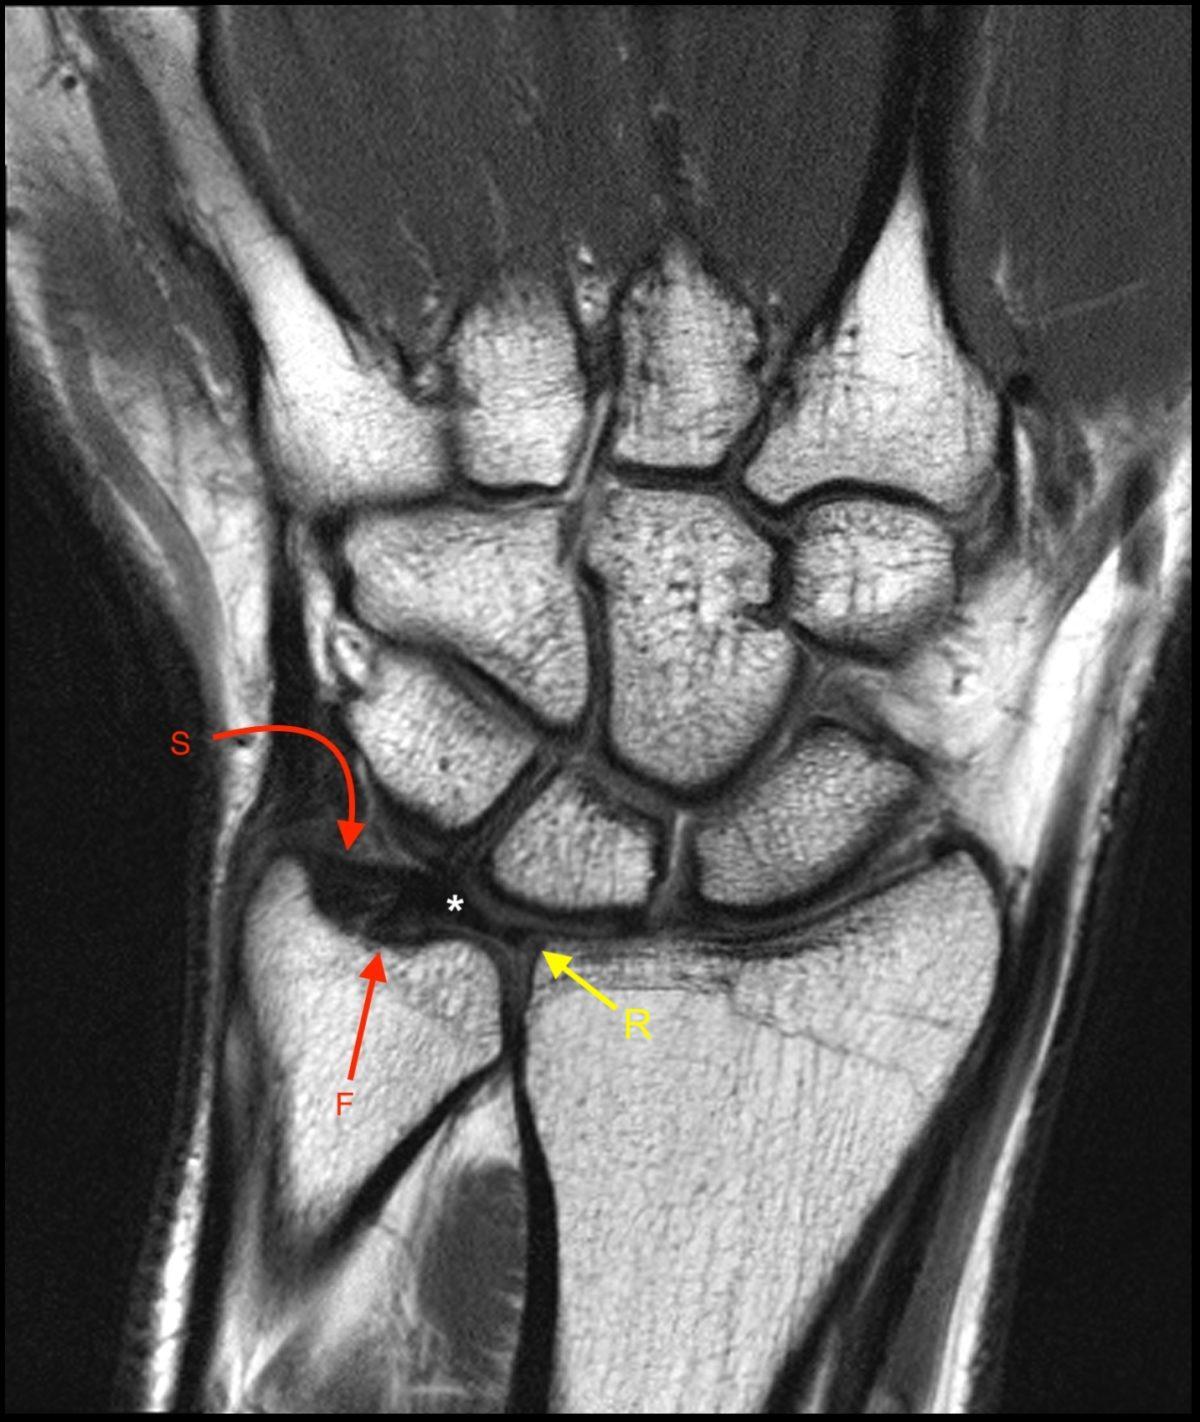

TRIANGULAR FIBROCARTILAGE COMPLEX MRI Sumer's Radiology Blog Triangular Cartilage Wrist Radiology Triangular fibrocartilage complex (tfcc) injuries may be traumatic or degenerative in nature. The anatomy, mri appearance, and clinical significance of the scapholunate ligament, lunotriquetral ligament, triangular fibrocartilage complex, carpal metacarpal ligaments, and volar and dorsal extrinsic ligaments are reviewed. The essential stabilizing structures of the wrist complex at the level of the distal radioulnar and radioulnocarpal joints consist of a. Triangular Cartilage Wrist Radiology.